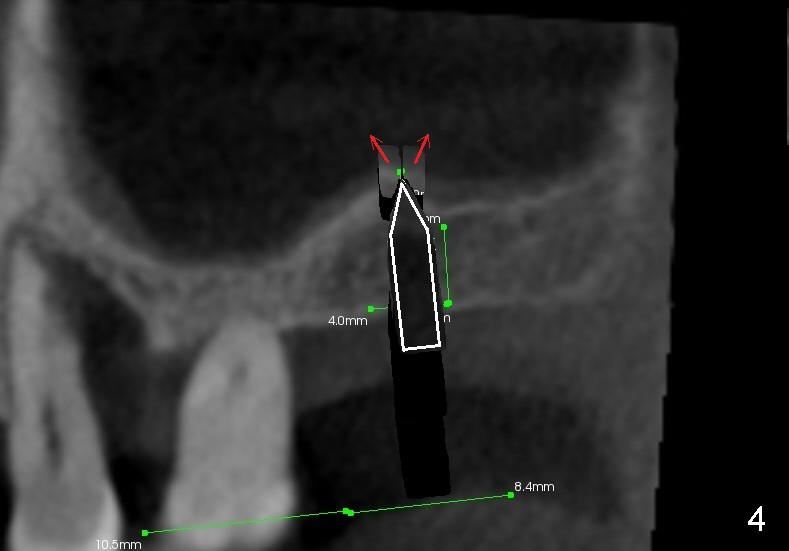

As the osteotome advances, some of the bone is brought apically (Fig.3 insert). The tapping with the thin osteotome should be stopped when penetration of the sinus floor is felt. The latter undergoes green stick fracture in a small area (Fig.4 arrows).

As the diameter of osteotomes increases (from 2, 3 to 4 mm), more of sinus

floor undergoes green stick fracture (Fig.5 pink arrows). At the same

time, more bone is brought apically (not shown). Finally a tapered

osteotome with flat end or tap is used to further lift the sinus floor (Fig.6

white arrow). This time the fractured bone fragments (red and pink arrows)

are more or less at the same level.